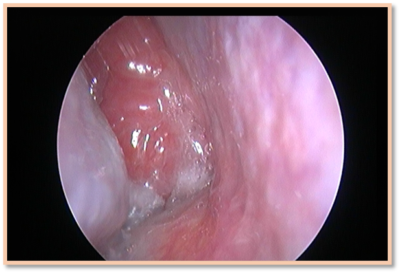

Figure 1 Endoscopic view of enlarged adenoid mass completely filling up and blocking the right choana.

Adenoid is a single mass of lymphoid tissue with its base on the posterior nasopharyngeal wall and its apex pointed toward the nasal septum. The surface is invaginated in a series of folds. It is covered by pseudostratified ciliated epithelium and is infiltrated by the lymphoid follicles.